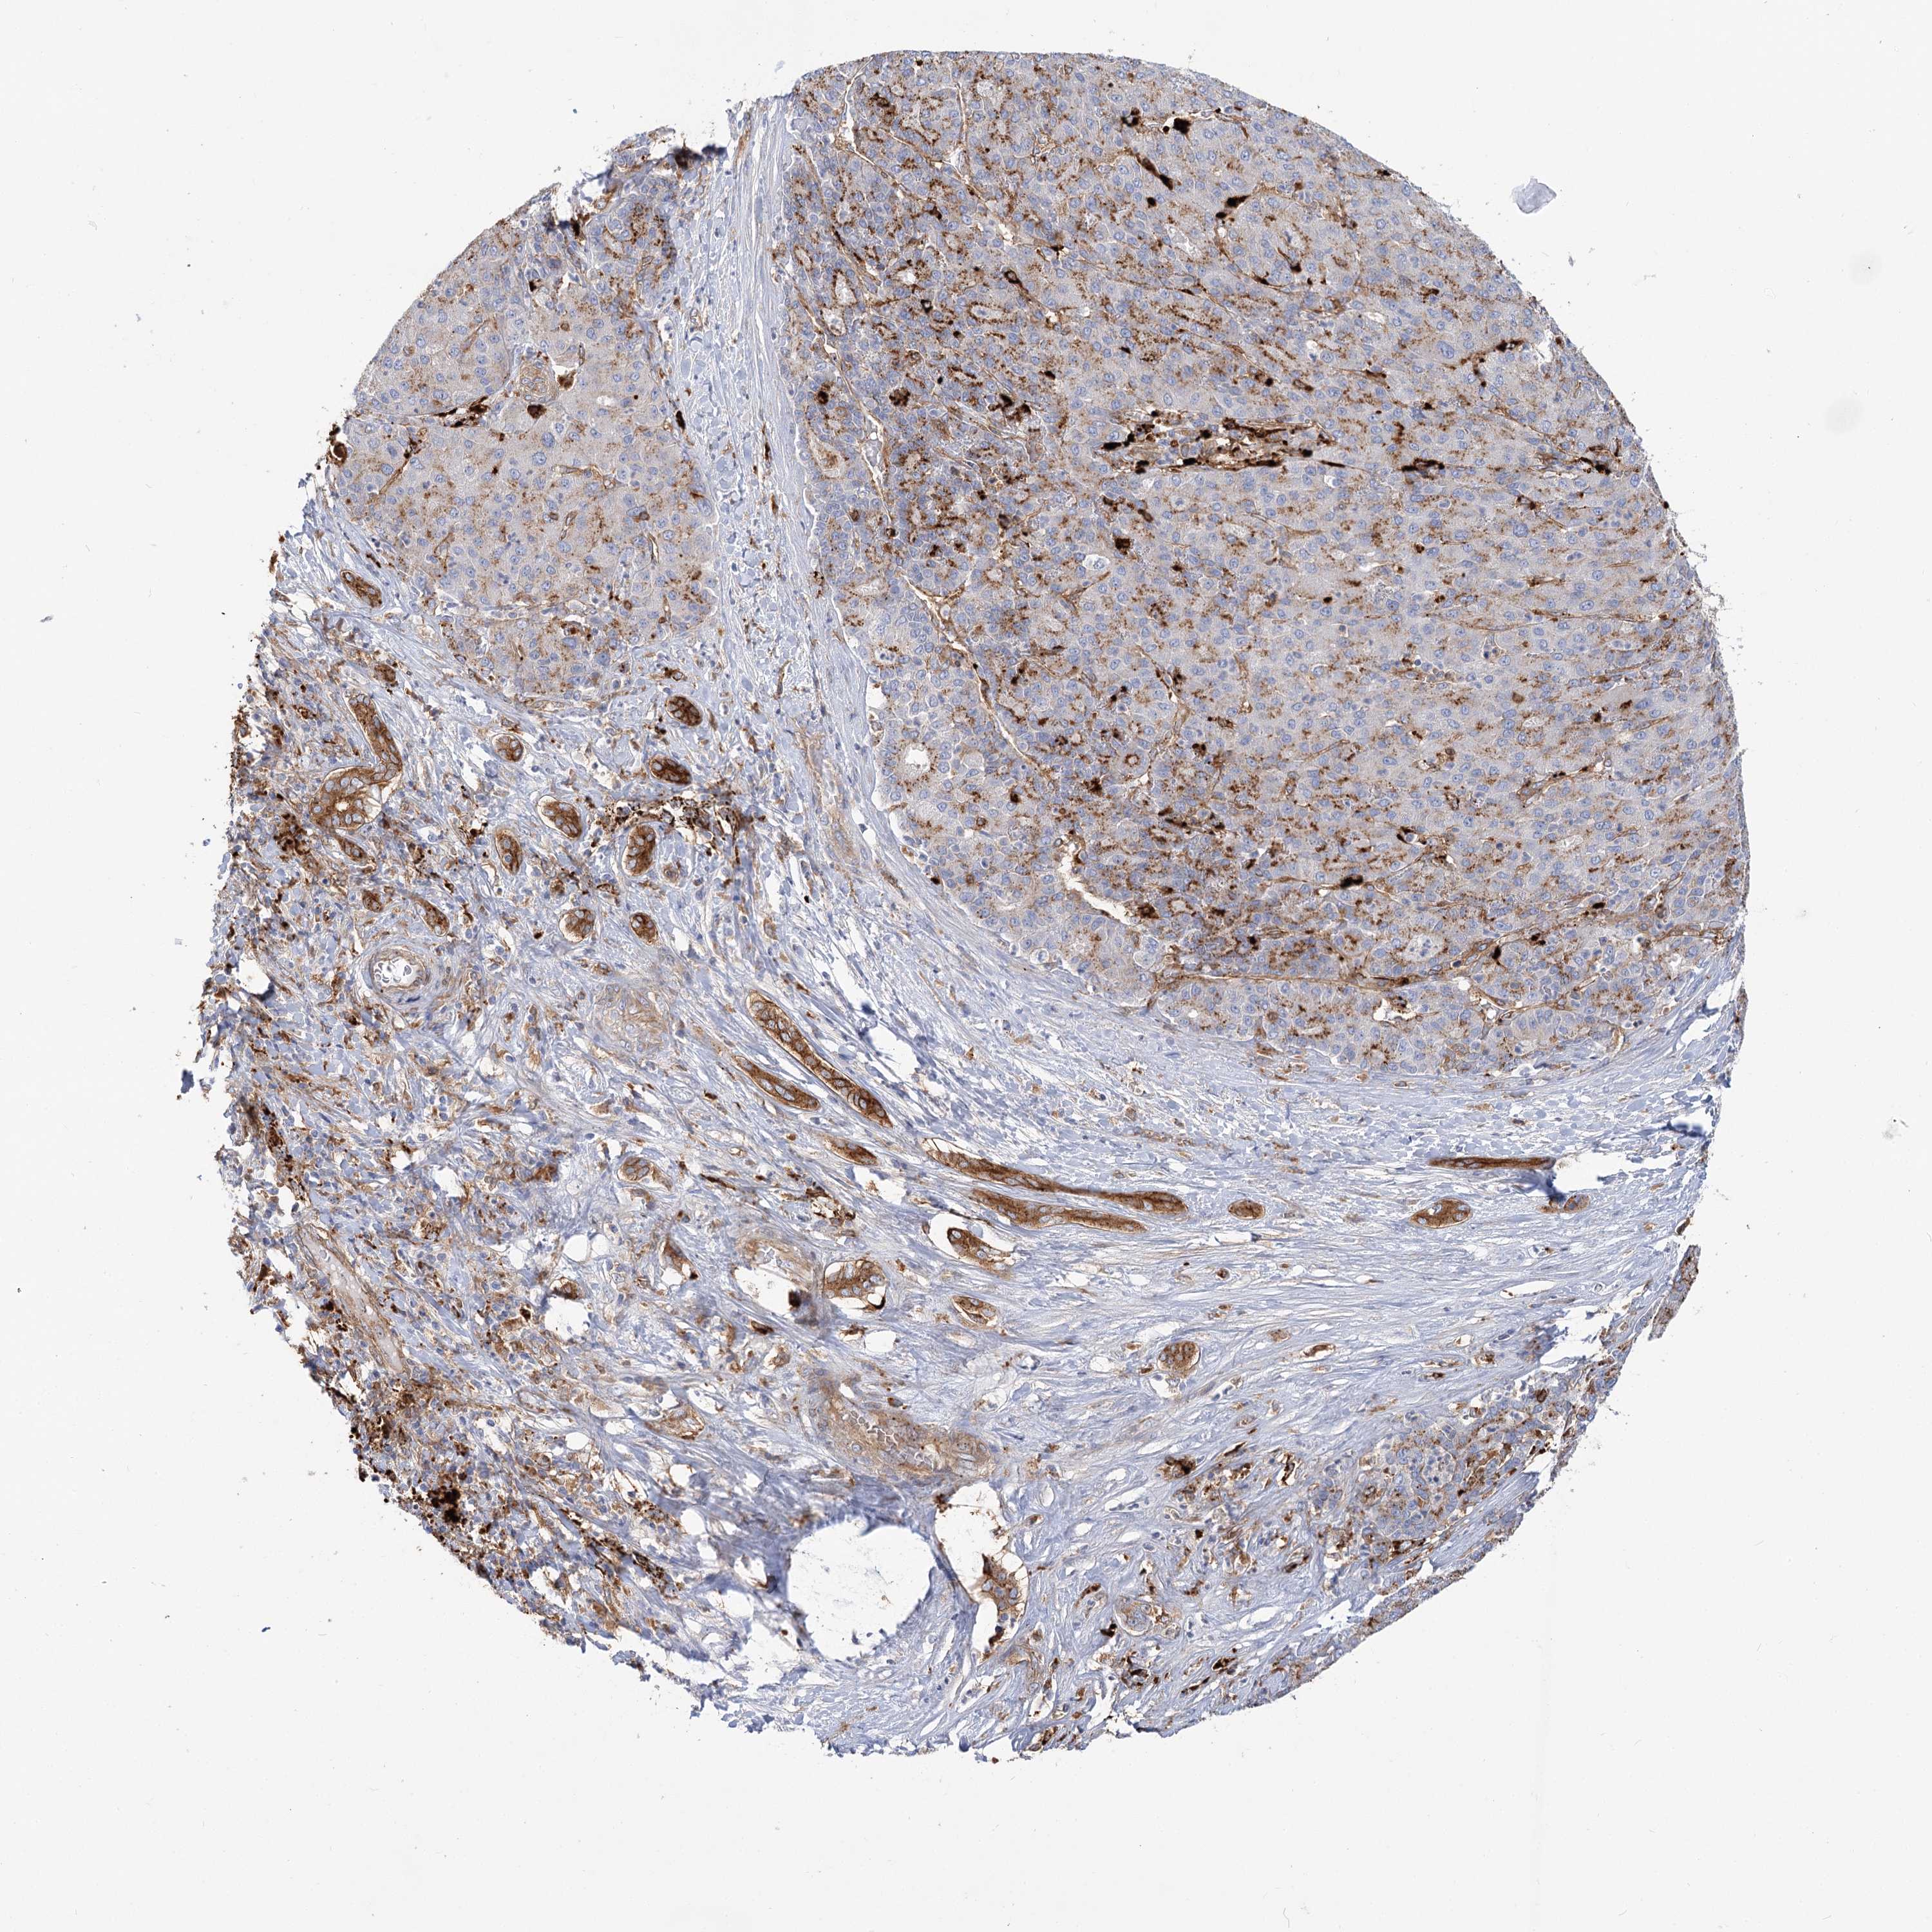

LIVER CANCER - Protein expressioni

A mouse-over function shows sample information and annotation data. Click on an image to view it in a full screen mode. Samples can be filtered based on level of antibody staining by selecting one or several of the following categories: high, medium, low and not detected. The assay and annotation is described here.

Antibody stainingi

Antibody staining in the annotated cell types in the current human tissue is reported as not detected, low, medium, or high, based on conventional immunohistochemistry profiling in selected tissues. This score is based on the combination of the staining intensity and fraction of stained cells.

Each image is clickable and will lead to virtual microscopy that enables deeper exploration of all samples and also displays staining intensity scores, fraction scores and subcellular localization as well as patient and tissue information for each sample.

Antibody HPA036322

Antibody HPA036323

Staining

High

Medium

Low

Not detected

Intensity

Strong

Moderate

Weak

Negative

Quantity

>75%

75%-25%

<25%

None

Location

Nuclear

Cytoplasmic/membranous

Cytoplasmic/membranous,nuclear

Cholangiocarcinoma

Carcinoma, Hepatocellular, NOS